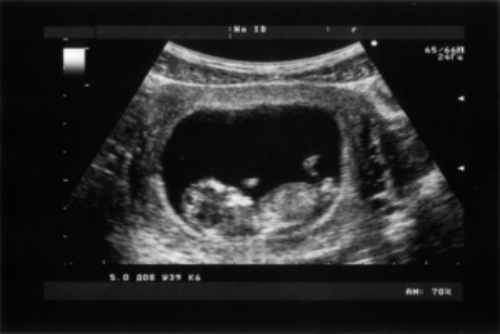

胎兒超聲檢查F4是什么意思—平創(chuàng)醫(yī)療

胎兒超聲檢查F4,指的是妊娠第4周胎兒超聲軟指標(biāo)第4期,在臨床上通常指胎兒已經(jīng)超聲檢查發(fā)現(xiàn)胎兒的心臟出現(xiàn)發(fā)育異常。胎兒超聲檢查F4,可能是心臟結(jié)構(gòu)異常、染色體異常、病毒感染等原因?qū)е?,胎兒出生后,需及時遵醫(yī)囑進行對癥治療。

超聲檢測1

胎兒超聲檢查F4,提示已經(jīng)出現(xiàn)畸形的情況,但情況較為少見。建議孕婦在妊娠第16周時進行唐氏篩查、羊水穿刺檢查,以明確胎兒是否存在異常。若明確胎兒存在異常,建議及時遵醫(yī)囑終止妊娠。